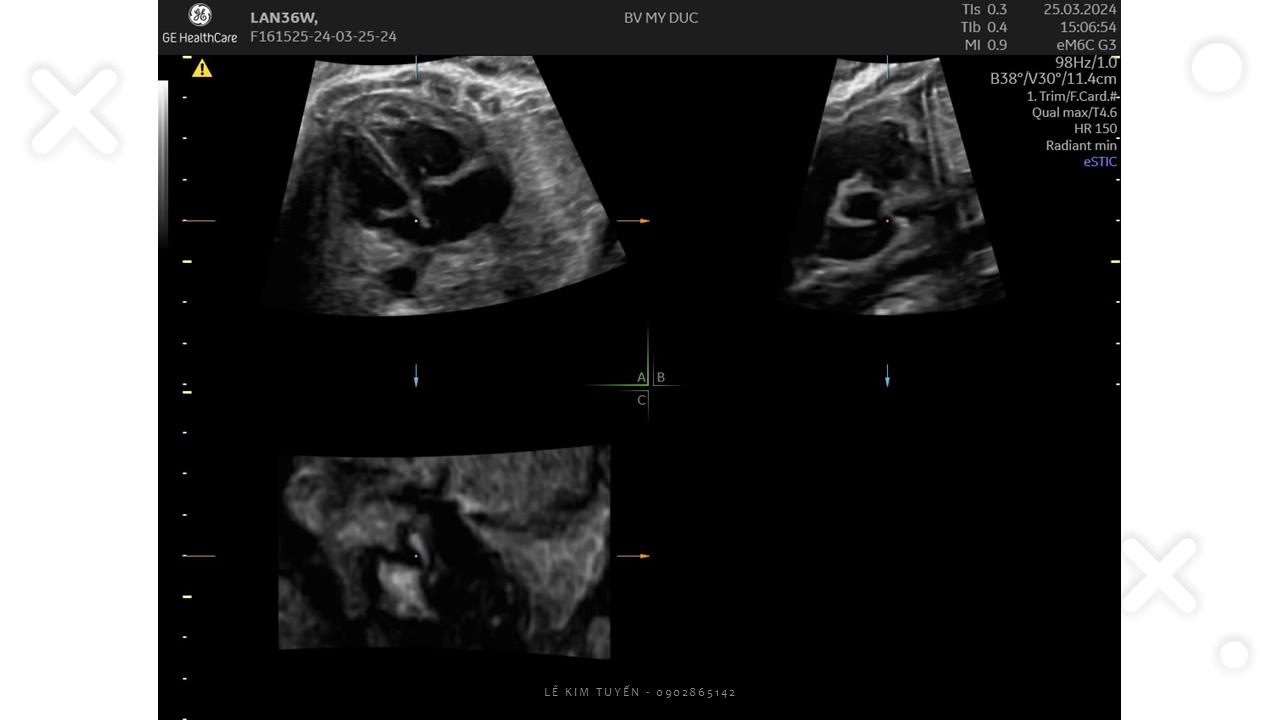

Siêu âm tim thai - Các kỹ thuật hiện đại

TS. BS. Lê Kim Tuyến

Bệnh viện Tim Tâm Đức